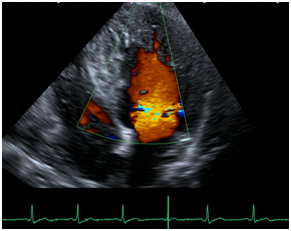

Enjoy the videos and music you love, upload original content, and share it all with friends, family, and the world on YouTube. Left ventricular noncompaction (LVNC) is a cardiomyopathy associated with sporadic or familial disease, the latter having an autosomal dominant mode of transmission. Echocardiographic short axis apical views of the left ventricle in a patient with non-compaction cardiomyopathy and a G4.5 mutation.

This gives the left ventricle a 'spongy' look (a bit like honeycomb). As normal development progresses, these trabeculated structures undergo significant compaction that transforms them from spongy to solid. These are best visualized on color flow Doppler of the left ventricle using apical windows.

The 2-dimentional echocardiography, 3-dimentional echocardiography, color Doppler echocardiography and contrast-enhanced echocardiography are of critical importance for diagnosis and family screening of NVM. Left ventricular noncompaction (LVNC) is a rare heart condition. Left ventricular noncompaction (LVNC) is a distinct phenotype characterized by prominent LV trabeculae and deep intertrabecular recesses .LVNC was previously also called spongy myocardium or hypertrabeculation syndrome but these terms should not be used interchangeably with LVNC .This review will focus on clinical manifestations and diagnosis of LVNC as an isolated disorder.

Non-compaction cardiomyopathy, is a rare congenital cardiomyopathy that affects both children and adults. Apical 4 chamber view shows multiple trabeculations and deep recesses at the ventricular apex. However, there are still many unknowns regarding its etiology and pathology, but also the.

Color Doppler In Lv Non Compaction Apical Four Chamber Views With Download Scientific Diagram